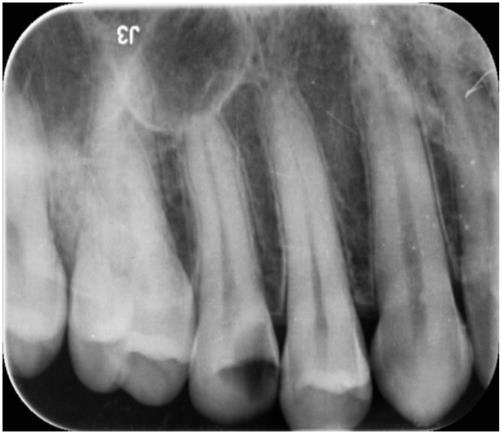

신경치료

Before

After

치아가 많이 썪은 경우 신경치료를 하고 치아를 살릴 수 있습니다.